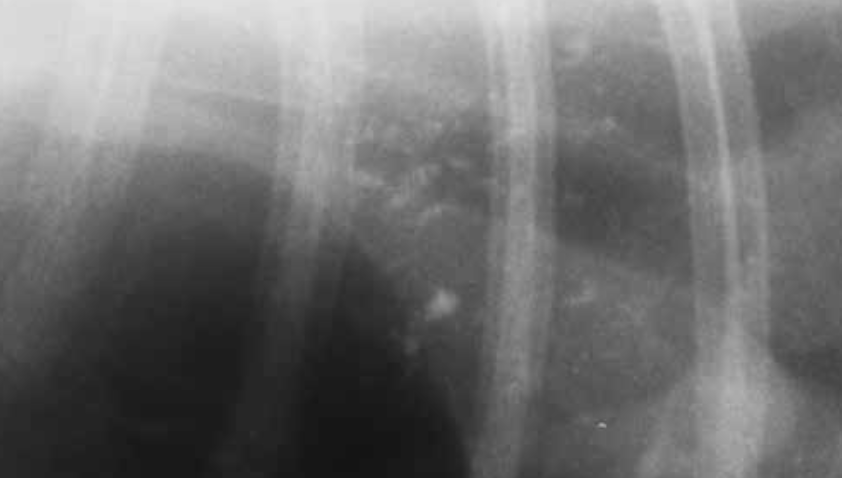

What should be suspected here in a 10y cat - this is the cranial lung?

A

Pulmonary neoplasia; mineralisation of tumours is common in cats.